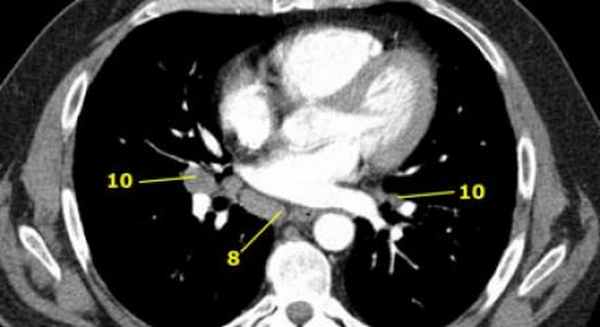

8. Параэзофагеальные лимфатические узлы

Эти лимфатические узлы ниже подкаринальных лимфатических узлов и распространяются каудальнее до диафрагмы.

На изображении слева ниже уровня карины справа от пищевода обозначен лимфатический узел 8 группы.

10. лимфатические узлы корня легкого

Лимфатические узлы корня расположены проксимальнее долевых узлов, но дистальнее медиастинальной дупликатуры и узлов промежуточного бронха справа.

Все лимфатические узлы 10-14 групп являются N1 узлами, так как они находятся вне средостения.